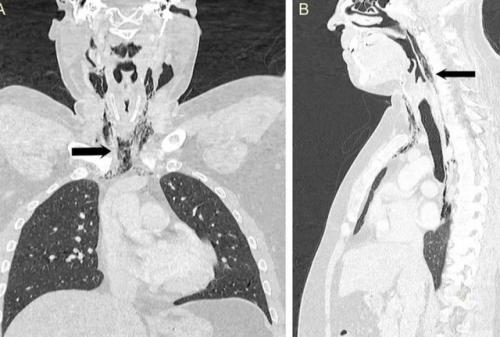

В попытке сдержать чих он почувствовал "Хлопок" в шее, за которым последовали боль и трудности при глотании. МРТ Показало, что воздух выходил через разрыв из трахеи в мягкие ткани шеи. В течение следующих нескольких дней мужчину кормили через зонд, чтобы дать тканям время для заживления.

Когда мы прикрываем нос и рот во время чихания, воздуху некуда деваться, и его давление разрывает мягкие ткани, нанося им вред.